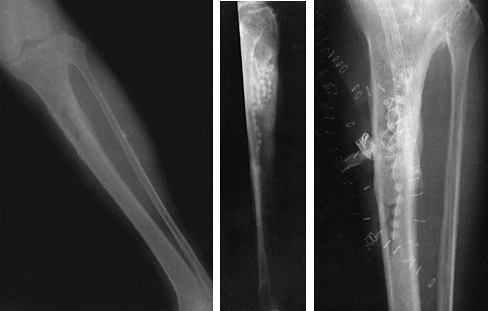

signal on the T2-weighted image sequences (Fig. 133.2, Fig. 133.3).

These are T1-weighted images of a 44-year-old woman with systemic lupus erythematosis and hematogenous osteomyelitis. There is decreased signal within the distal third of the tibia and a serpiginous area of low intensity consistent with osteonecrosis. A biopsy had been performed previously. At surgery, she had an abscess with sequestra. |

Figure 133.3.

These T2-weighted images of a 15-year-old boy show increased signal from the ankle to the mid tibia. There is increased signal in the adjacent soft tissues about the ankle and tibia. There is a minimal ankle effusion present. At surgery, the patient had an intramedullary abscess of the metaphysis and distal tibia. |